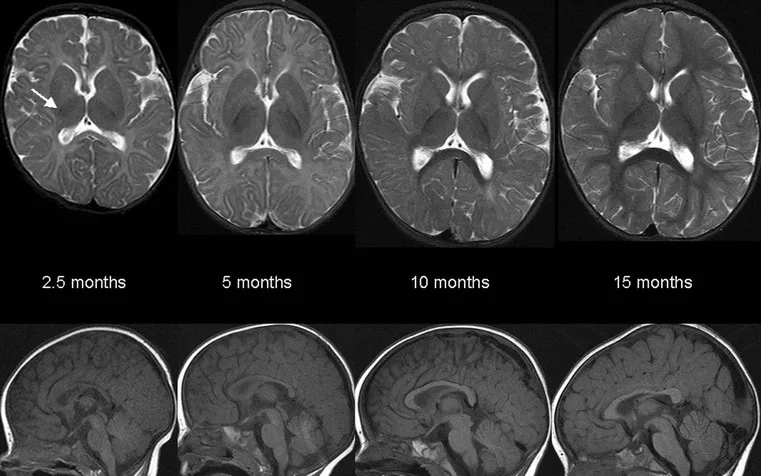

- Myelination (Birth - ~2 yrs): Pattern: Caudal→cranial, posterior→anterior, central→peripheral.

- MRI: T1W ↑ (hyperintense), T2W ↓ (hypointense) with maturation.

- Posterior Limb Internal Capsule (PLIC) myelinated by 7 months. Largely complete by 2 years.